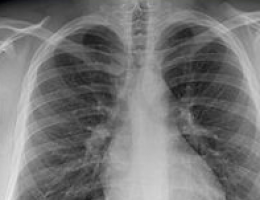

Tripling tobacco tax globally would cut smoking by a third, and prevent 200 million premature deaths this century from lung cancer and other diseases, according to a Cancer Research UK review published in the New England Journal of Medicine.

In the European Union, tobacco now causes 300,000 deaths a year under the age of 70 (250,000 men, 50,000 women). An EU-wide doubling of cigarette prices would prevent 100,000 deaths a year in the under 70s.